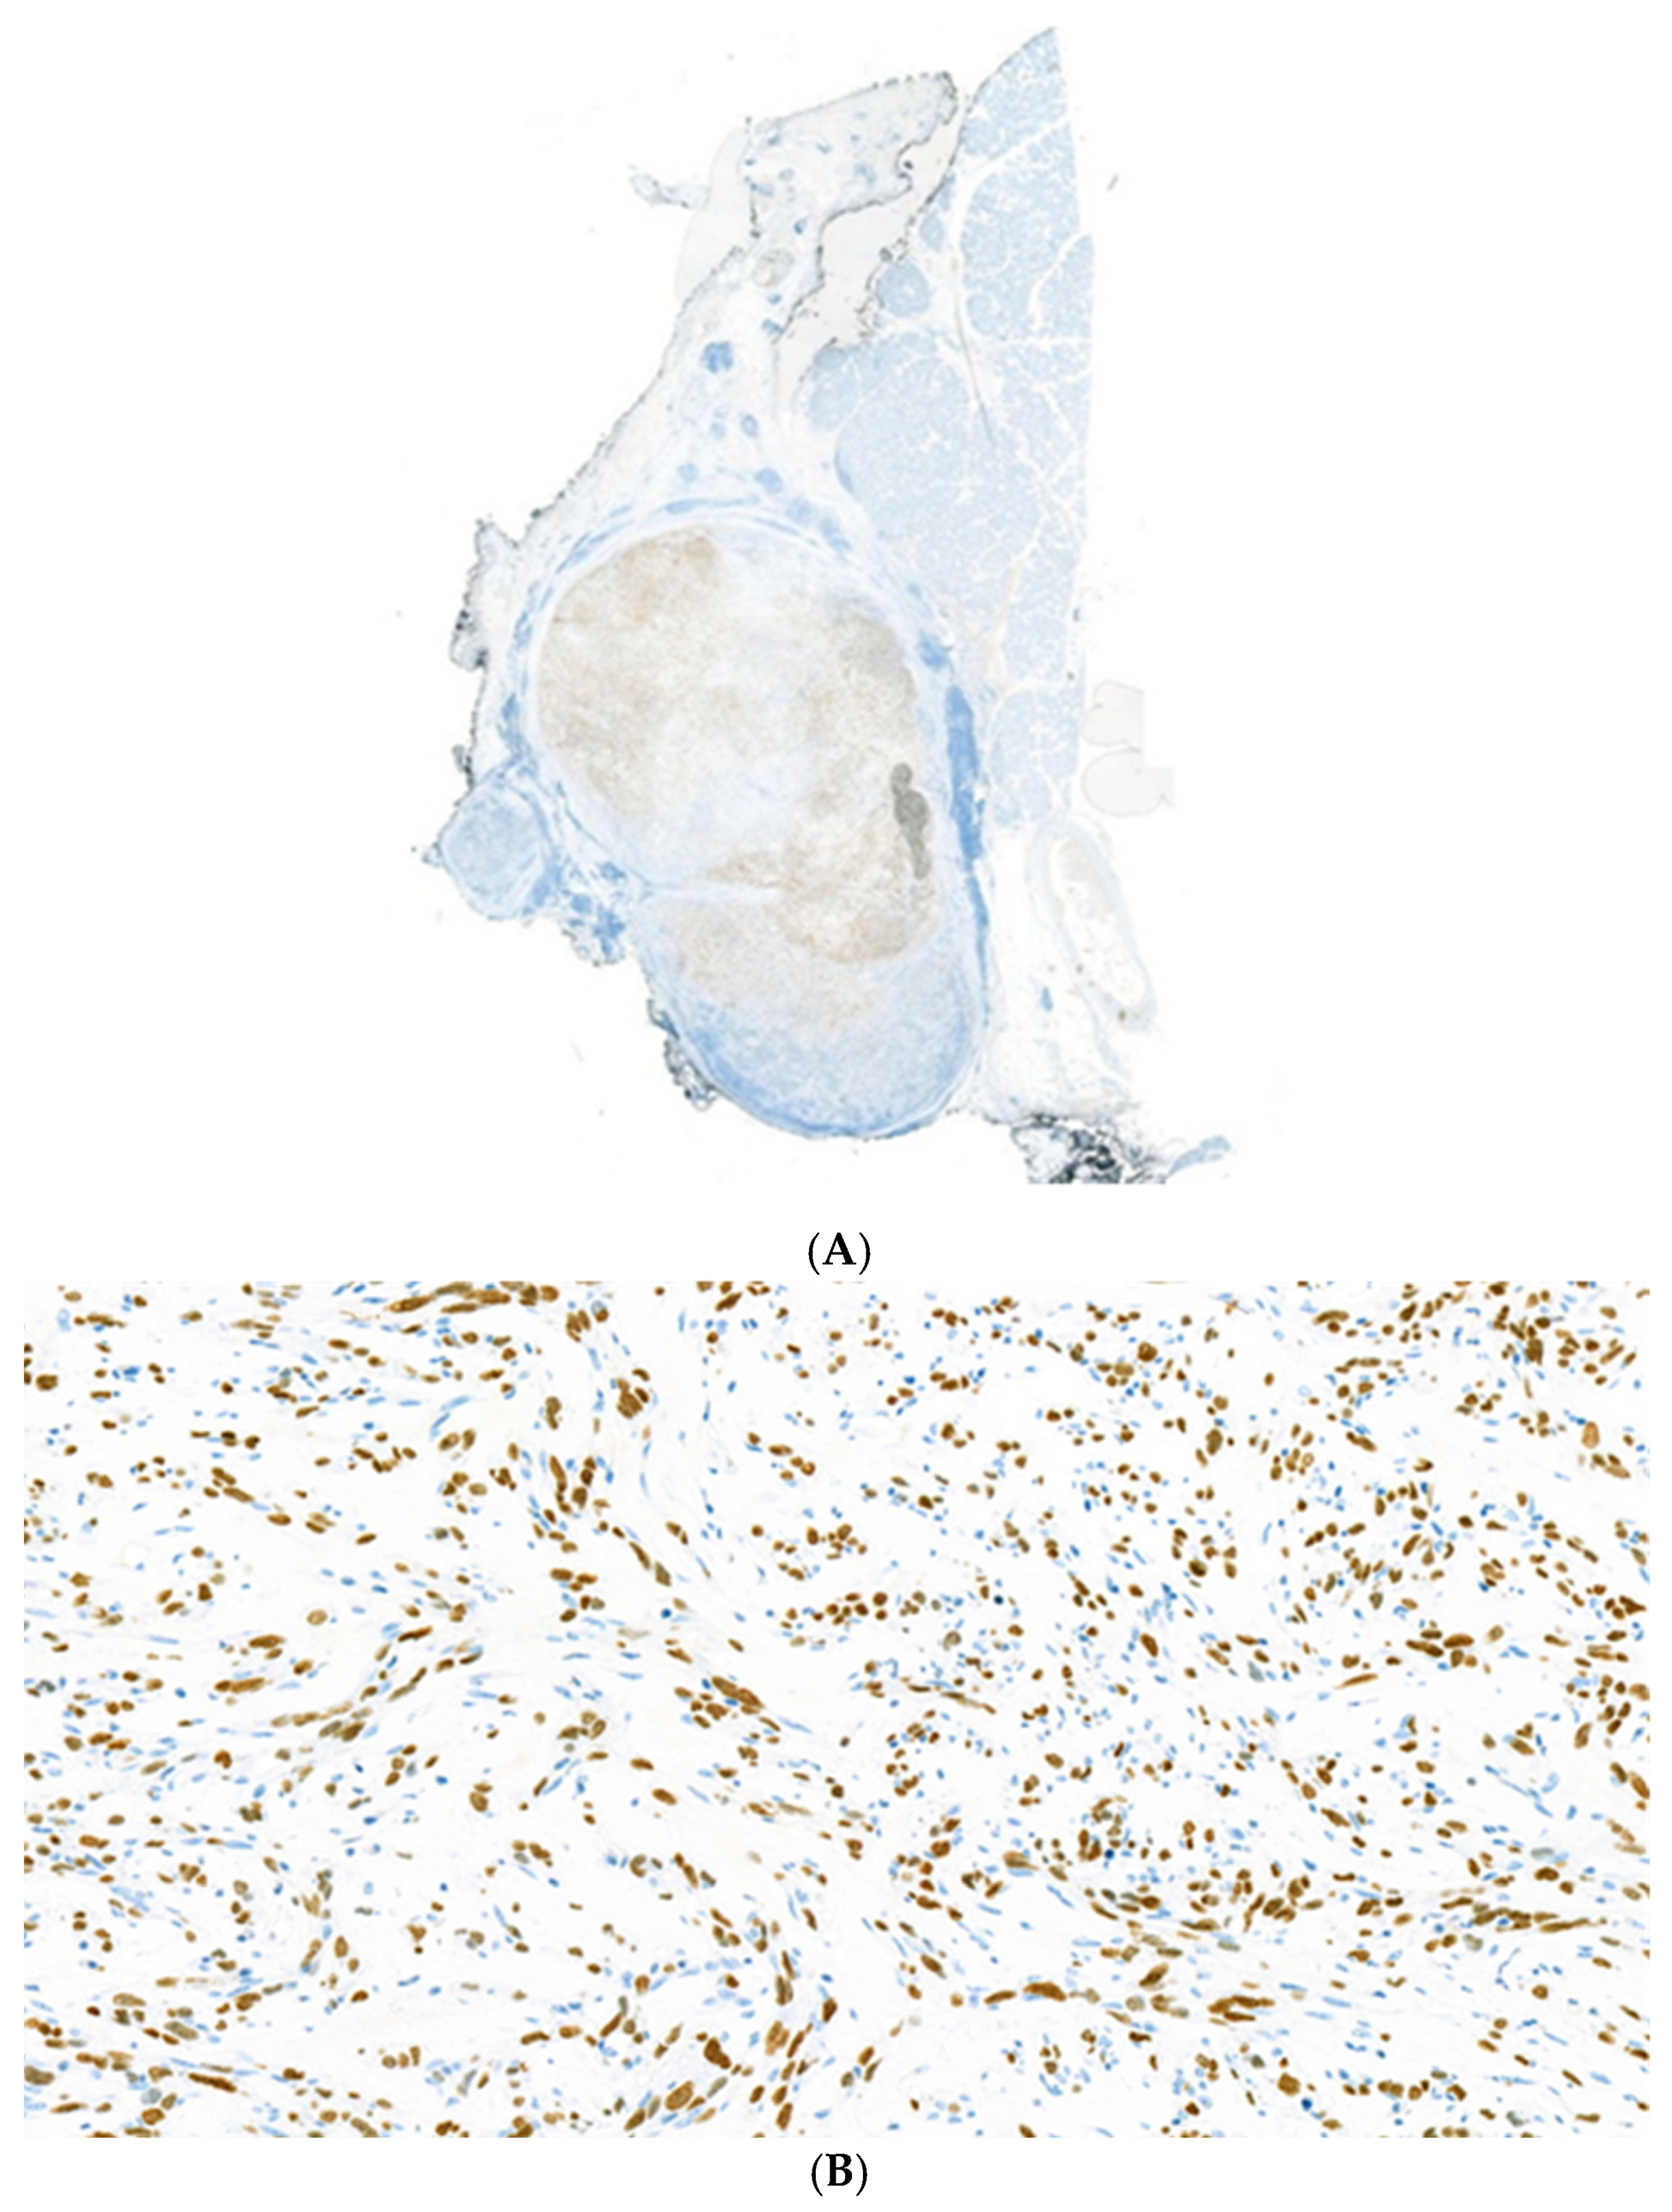

Figure 4. A strong and widespread S-100 positivity is detected within the tumour. The tumour cells are strongly and diffusely immunoreactive with the S-100 protein, exhibiting both nuclear and cytoplasmic staining (A). The tumour cell nuclei showed a strong and extensive positivity by SOX10 immunohistochemistry (B). SOX10 = SRY-Box Transcription Factor 10.